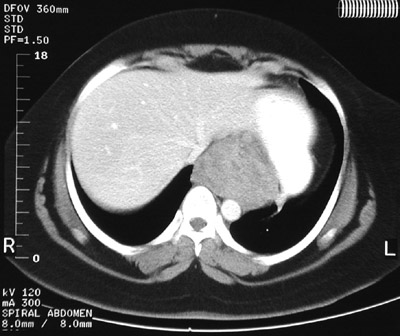

| There is a large mass involving the lower esophagus and extending to the upper gastric fundus in these abdominal CT scan views in the lower chest above and upper abdomen below. This is a gastrointestinal stromal tumor (GIST). These tumors are composed of spindle cells. The biologic behaviour is unpredictable. |